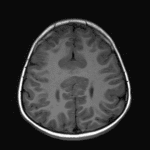

Middle Interhemispheric Variant (MIHV) of Holoprosencephaly

Findings

- Fusion of the thalami at midline and cross-hemispheric fusion of supracallosal gyri with abnormal cortical thickening

- Abnormal cortical thickening along the posterior aspects of the right greater than left sylvian fissures with polymicrogyria

- Azygos anterior cerebral artery

Constellation of findings most consistent with middle interhemispheric variant (MIHV) of holoprosencephaly including: absent septum pellucidum, thinned and dysmorphic appearance of the body and isthmus of the corpus callosum, fusion of the thalami at midline, and cross-hemispheric fusion of supracallosal gyri.

Abnormal cortical thickening and polymicrogyria along the posterior aspects of the right greater than left sylvian fissures as well as abnormal cortical thickening of the bridging supracallosal gyri, all potentially representing possible epileptogenic foci.

- Sylvian fissures oriented vertically connecting across the midline over the vertex

- Cortical dysplasias, heterotopias

- Azygos anterior cerebral artery